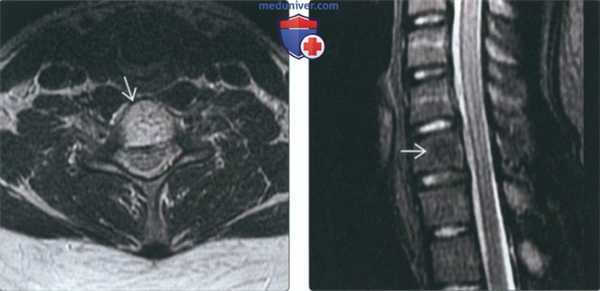

(Слева) На аксиальной МРТ (Т2 ВИ) отчетливо определяются ожидаемые признаки гемангиомы позвонка. В изоинтенсивном объемном образовании ограниченным телом позвонка, визуализируются трабекулы и жировая ткань.

(Справа) На сагиттальной MPT (STIR) определяется полное подавление сигнала в типичной гемангиоме, целиком представленной жировой тканью. Картина гемангиомы на Т2 ВИ вариабельна и зависит от жировых и сосудистых элементов.